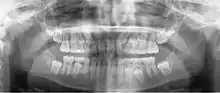

أشعة بانوراما

صورة الأشعة البانورامية أو التَّصْويرُ الشُّعاعِيُّ البانُورامِيّ (بالإنجليزية: panoramic radiograph) هي أشعة سينية بانورامية لفحص الأسنان للفكين العلوي والسفلي. تكون الصورة ثنائية الأبعاد لنصف دائرة من الأذن إلى الأذن. التصوير الشعاعي البانورامي هو شكل من أشكال التصوير المقطعي للمستوى البؤري. وهكذا يتم التقاط صور من عدة مستويات لعمل الصورة البانورامية المركبة، حيث يكون الفك العلوي والفك السفلي في النطاق البؤري والأجسام السطحية والأعمق من النطاق غير واضحة.